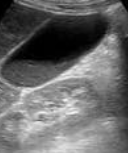

Her postoperative course was uneventful; however, on the 9th postoperative day, she developed septic-type fever and tenderness in the right hypochondrium. Thorough clinical, laboratory, and imaging investigation revealed the presence of acalculous cholecystitis (thickened gallbladder wall and presence of biliary sludge).